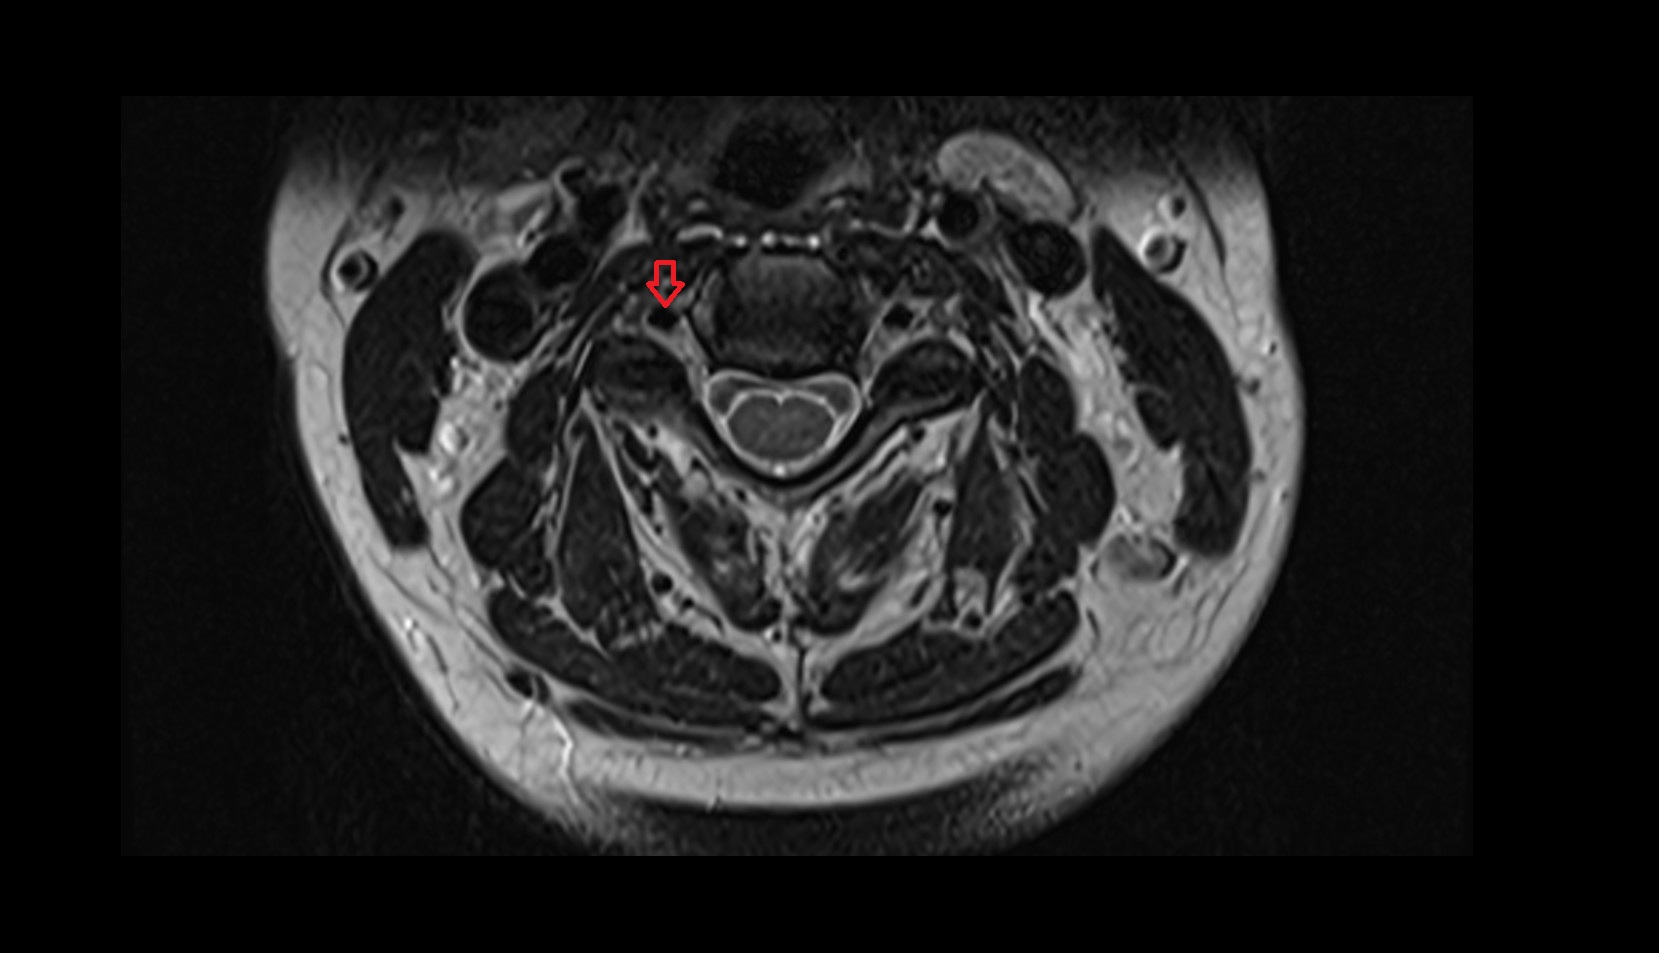

- Spinal cord

- Upper cervical spinal cord

- Cervical spinal nerve 1 (C1)

- Cervical spinal nerve 2 (C2)

- Cervical spinal nerve 3 (C3)